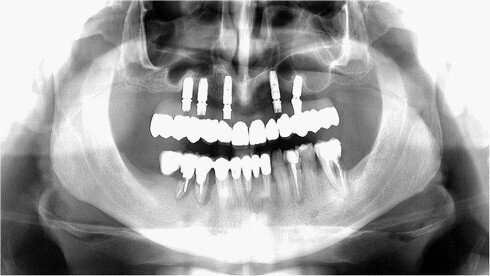

Panoramatický RTG snímek po zavedení implantátů

Stanko: „V době zákroku u Nina bylo naším chirurgickým protokolem zavedení 6 implantátů bez okamžitého zatížení se snímatelnou provizorní náhradou a po době hojení 3–4 měsíce reoperační umístění vhojovacích abutmentů. V Ninově případě jsme měli velmi omezený objem kosti a bylo naplánováno umístění jen 5 kratších implantátů, v případě nutnosti s augmentací sinus liftu. Nebyl brán zřetel na primární stabilitu implantátů, protože náš protokol v danou chvíli nespočíval v jejich okamžitém zatížení.“